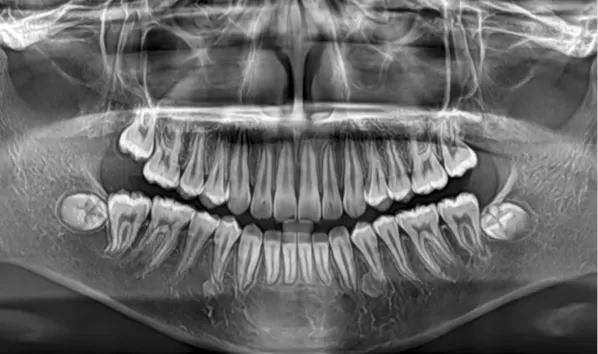

Rayons X avant le traitement

[Radiographie panoramique/Céphalogramme latéral]